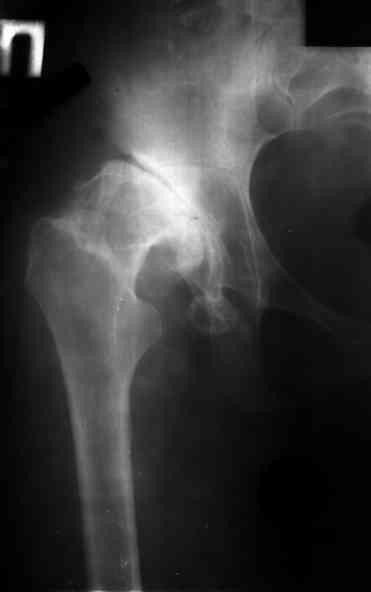

Ув. коллеги, женщина, 37 лет, имеет диспластический коксартроз. Сомневается в положительном результате от эндопротезирования, но хочет оперироваться. Что порекомендуете? С ув. Sergey A. Melashenko ул. Кирова 88-А, г. Приморск, Запорожская обл., 72100, Украина

Оперироваться. Альтернативы нет. Надо делать обе ноги, поочередно с реконструкцией крыш для последующей удобной ревизии. Ножки бесцементные.

Сергей. Операция первичного эндопротезирования предусматривает у данной больной (я бы сделал так) - 1. Доступ с хорошим обзором впадины (или задний

или с пересечением б.вертела) - затем установку тазового компонента с одномоментной пластикой крыши вертлужной впадины из утилизируемой головки

(если получится бесцементная чаша - это лучше, но не факт - вероятно будет моделирующее кольцо с цементируемой чашей - внимание к "версии" чаши) -

затем классическая бесцементная ножка. Справа будет попроще. Слева рассчет после установки правого сустава. Может потребоваться двухэтапное

протезирование. При отсутствии проблем с финансировании - отправьта в Харьков - Киев - Донецк. С уважением. А Рыков.

1. при таком анатомическом варианте корригирующие остеотомии явно проигрывают тотальному эндопротезированию.

2. первым этапом оперируем сторону с преобладающим болевым.

3. справа может быть будет достаточно структурного аутотрансплантата, но вариант с кольцом надо иметь в виду; слева использовал бы армирующую конструкцию (плохая надацетабулярная кость - проблемное приживление трансплантата).

4. вероятность осложнений выше, чем в банальной ситуации, правильно дама беспокоится, лучше делать операцию там, где это на потоке. Если ближе не найдется, присылайте.